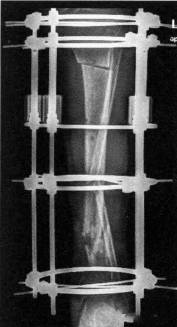

对严重粉碎性骨折或骨缺损,可延伸固定杆以维持原肢体长度,即牵伸固定。